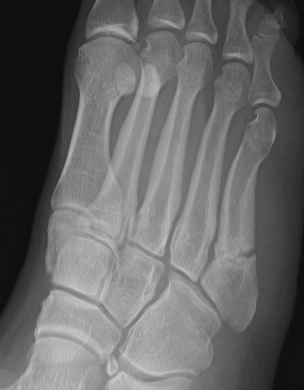

Xray

Zone 2 fractures

Union of zone 2 fracture with nonoperative care

Progression to nonunion of zone 2 fracture with nonoperative care

Zone 3 Fractures

Progression to nonunion of zone 3 fracture with nonoperative care

Torg Classification

| Type I | Type II | Type III |

|---|---|---|

| Acute | Delayed union | Nonunion |

|

Narrow fracture line No sclerosis No cortical reaction No periosteal hypertrophy |

Increased fracture line Both cortices Some sclerosis Some periosteal hypertrophy |

Significant sclerosis Significant cortical hypertrophy |